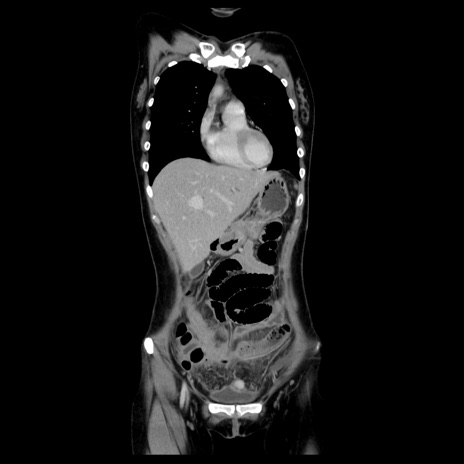

症例39(冠状断像)

【症例】40歳代女性

【主訴】上下腹部痛

【現病歴】2日目から下腹部痛あり。夜間は痛みで眠れなかった。昨日より上腹部痛と下痢が出現。臥位で痛みは軽快したため、休んでいた。本日になって臥位でも立位でも痛みが強くなってきたため救急要請。

【既往歴】子宮内膜症

【身体所見】部:平坦・軟、左上下腹部に圧痛あり、反跳痛あり。

【データ】WBC 21800、CRP 26.78

MRI(4日後)